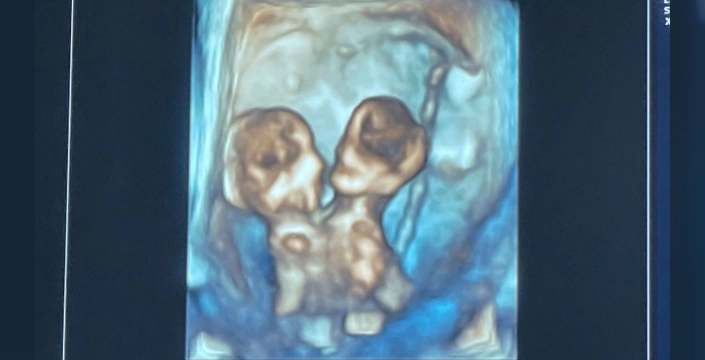

ABD'nin Michigan eyaletinde yaşayan Nicole ve Austin LeBlanc çifti, ilk kez bebek sahibi olacaklarının öğrenmesiyle büyük bir mutluluk yaşadı. Ancak, gebeliğin yedinci haftasında beklenmedik bir durum ortaya çıktı. Doktorlar, sadece bir kalp atışı duymalarına rağmen ultrason görüntülerinde ikiz bebekler tespit etti. Kısa süre sonra Nicole, şiddetli karın ağrısıyla hastaneye kaldırıldı ve yapılan detaylı ultrason sonucunda gerçek ortaya çıktı: Nicole, birbirine yapışık ve aynı kalbi, karaciğeri, bağırsakları, diyaframı ve göbek kordonunu paylaşan ikiz kız bebeklerine hamileydi.

Annelerinin bu kararının ardından, 32. haftada Maria Therese ve Rachel Clare sezaryenle dünyaya geldi. Nicole, doğum anını şöyle anlattı: 'Maria yüksek sesle ağladı, Rachel ise uyuyordu. Onların küçük yüzlerini ve paylaştıkları bedeni görmek inanılmazdı.' Ne yazık ki, ikizler doğduktan hemen sonra anne ve babalarının kucağında hayatlarını kaybettiler.